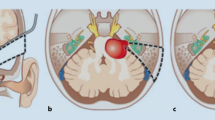

In NF2 patients, the disc electrode is placed on the surface of the cochlear nucleus complex on the dorsolateral surface of the brainstem, immediately rostral to the pontomedullary junction, through a standard translabyrinthine approach following removal of the vestibular schwannoma. The cochlear nucleus is composed of the DCN and the VCN. As shown in Fig. 18.1, both the DCN and VCN are located adjacent to the lateral recess of the fourth ventricle near the foramen of Luschka. The cochlear nucleus has few visible surface landmarks; therefore, the surrounding structures, such as the root entry point of cranial nerve VIII, cranial nerve VII, the choroid plexus, cranial nerve IX, and the tela choroidea, are important guides for placing the electrode array accurately on the surface of the cochlear nucleus. Many surgeons prefer to place the electrode array of the ABI within the lateral recess to stimulate the DCN and the intraventricular part of the VCN (Fig. 18.1). In addition to the anatomical landmarks surrounding the cochlear nucleus, intraoperative monitoring of EABR using ABI-mediated stimuli is used to correctly place the electrode array on the cochlear nucleus. In non-NF2 patients, neurosurgeons prefer the retrosigmoid approach to the translabyrinthine approach because it is more familiar to them and the labyrinth and auditory nerve can be preserved.

(a) Cross section of pontomedullary junction at level of lateral recess of the fourth ventricle (4th Vent.). DCN (Dorsal Coch. Nucl.) and VCN (Ventral Coch. Nucl.) are located adjacent to the lateral recess (Lat. Recess) of the fourth ventricle. DCN underlies a prominence, while VCN is more deeply imbedded in brainstem and does not produce as great a prominence on surface of brainstem. (b) Retrosigmoid view. Flocculus has been elevated to expose junction of vestibulocochlear nerve with side of brainstem at pontomedullary junction. Foramen of Luschka (For. Luschka), which is positioned dorsal to glossopharyngeal nerve (CNIX), is partially covered by choroid plexus. (c) Choroid plexus has been retracted rostrally to expose dorsal cochlear nucleus sitting in floor of lateral recess. Ventral cochlear nucleus is positioned in area between lateral edge of dorsal cochlear nucleus and junction of vestibulocochlear nerve (CN VIII) with brainstem [16]